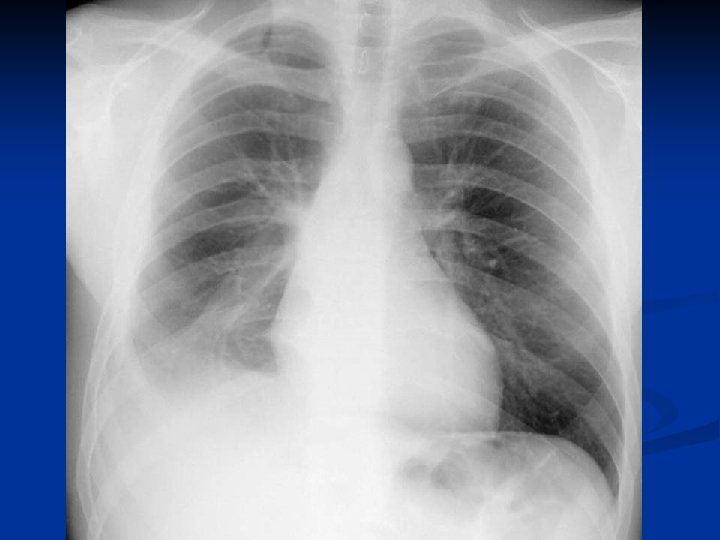

Metode de diagnosticare

Concluzii n n n CHP evolueaza mult timp asimptomatic sau cu simptome nespecifice. Diagnosticul

Concluzii n n n CHP evolueaza mult timp asimptomatic sau cu simptome nespecifice. Diagnosticul precoce este deosebit de important avand in vedere evolutia acestei boli. Tratamentul medical antiparazitar (Albendazol) este indicat postoperator. Rezectia pulmonara este o metoda de rezerva in tratamentul chirurgical al CHP. Indicatia operatorie este absoluta, tehnica operatorie alegandu-se in functie de caracteristicile fiecarui caz in parte.